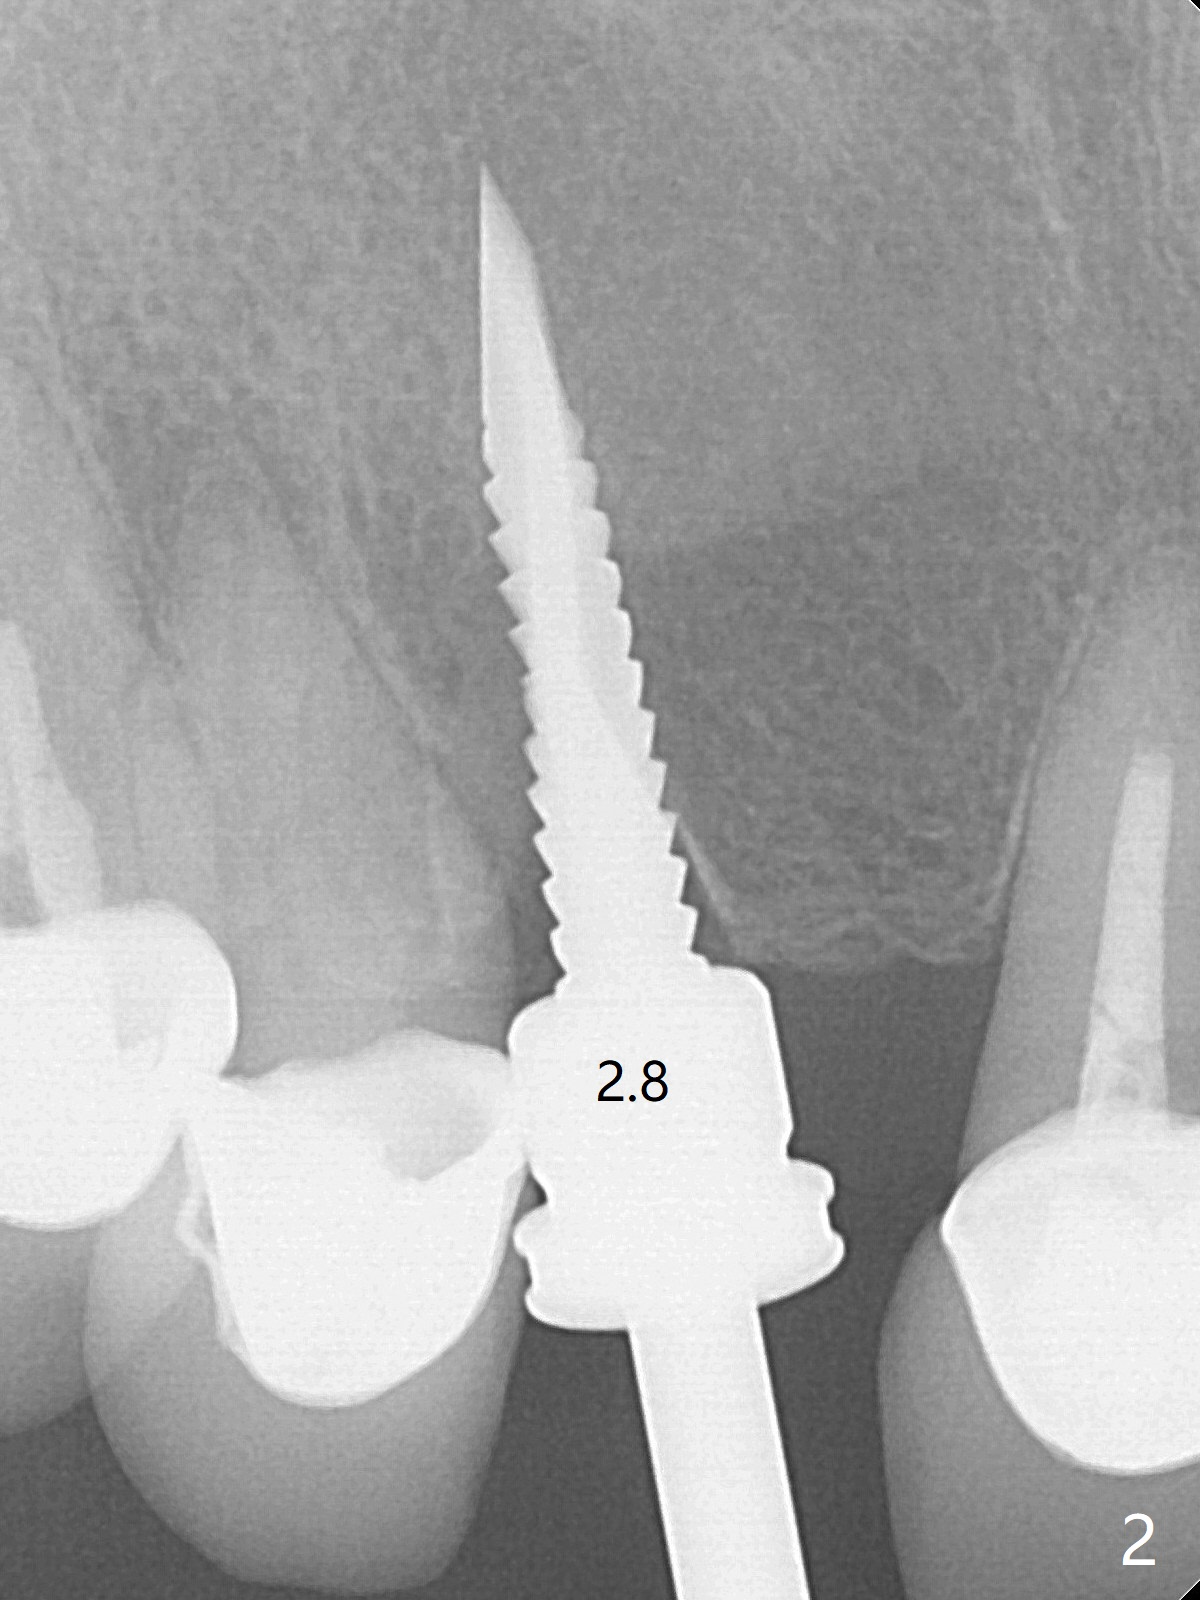

To reduce the large black triangle between the lateral incisor/canine and central incisor (Fig.1 *), osteotomy is not established mesial enough initially (Fig.2). Since the bone density is not high, trajectory change is not attempted. The ridge is wider within the socket. A relatively large 2-piece implant (3.5x13 mm) is placed (Fig.3), but a 4x5.7(2) mm abutment is incompletely seated (<). Use of 4.6 and 5.6 mm bone profile drills does not appear to solve the problem. The implant is backed up to the supra-gingival level so that it seems easier physically to insert the same abutment into the implant. Then both of them are torqued into the place together (Fig.4). An immediate provisional is fabricated to close the gingival embrasure as much as possible (Fig.5). Consider reducing the provisional margin (arrow) as early as possible postop. In fact the patient agrees to have a new crown made for #8 to further close the embrasure. The bone graft remains in place 4 months postop (Fig.6). The gingiva is healthy around the provisional 4.5 months postop (Fig.7). The gingival embrasure with a permanent restoration is smaller than that before treatment (Fig.8). Return to No Deviation Prevent Screw Loosening Prosthetic Planning Kit Webinars Xin Wei, DDS, PhD, MS 1st edition 02/11/2020, last revision 07/09/2020